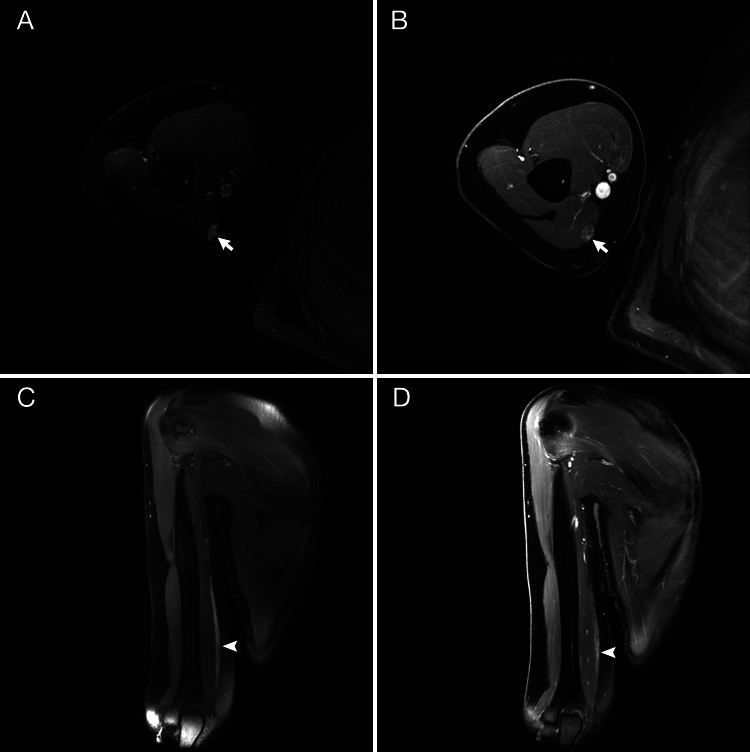

Observations: A 48-year-old woman with a history of localized amyloidosis to the orbital muscle 2 years earlier presented with new neurological symptoms. Extensive evaluations including skin, muscle, and distal cutaneous nerve biopsies were negative, and empirical treatment trials did not improve her condition. An MRI-guided targeted biopsy of the right ulnar nerve in the distal arm was planned. During surgery, a medial triceps branch arising from the ulnar nerve was identified and was biopsied along with a neighboring fascicle of the ulnar nerve to the flexor carpi ulnaris. The pathology of the ulnar nerve fascicle but not the contiguous triceps branch showed amyloid (AL [kappa] subtype on mass spectroscopy). The patient was started on treatment.

Lessons: The positive biopsy of the ulnar nerve fascicle allowed targeted treatment of the neural amyloidosis. While the negative biopsy of the triceps branch could be attributed to sampling error, it could also be due to the fact that this branch found within the ulnar nerve is thought to originate from the radial nerve. https://thejns.org/doi/10.3171/CASE25484.